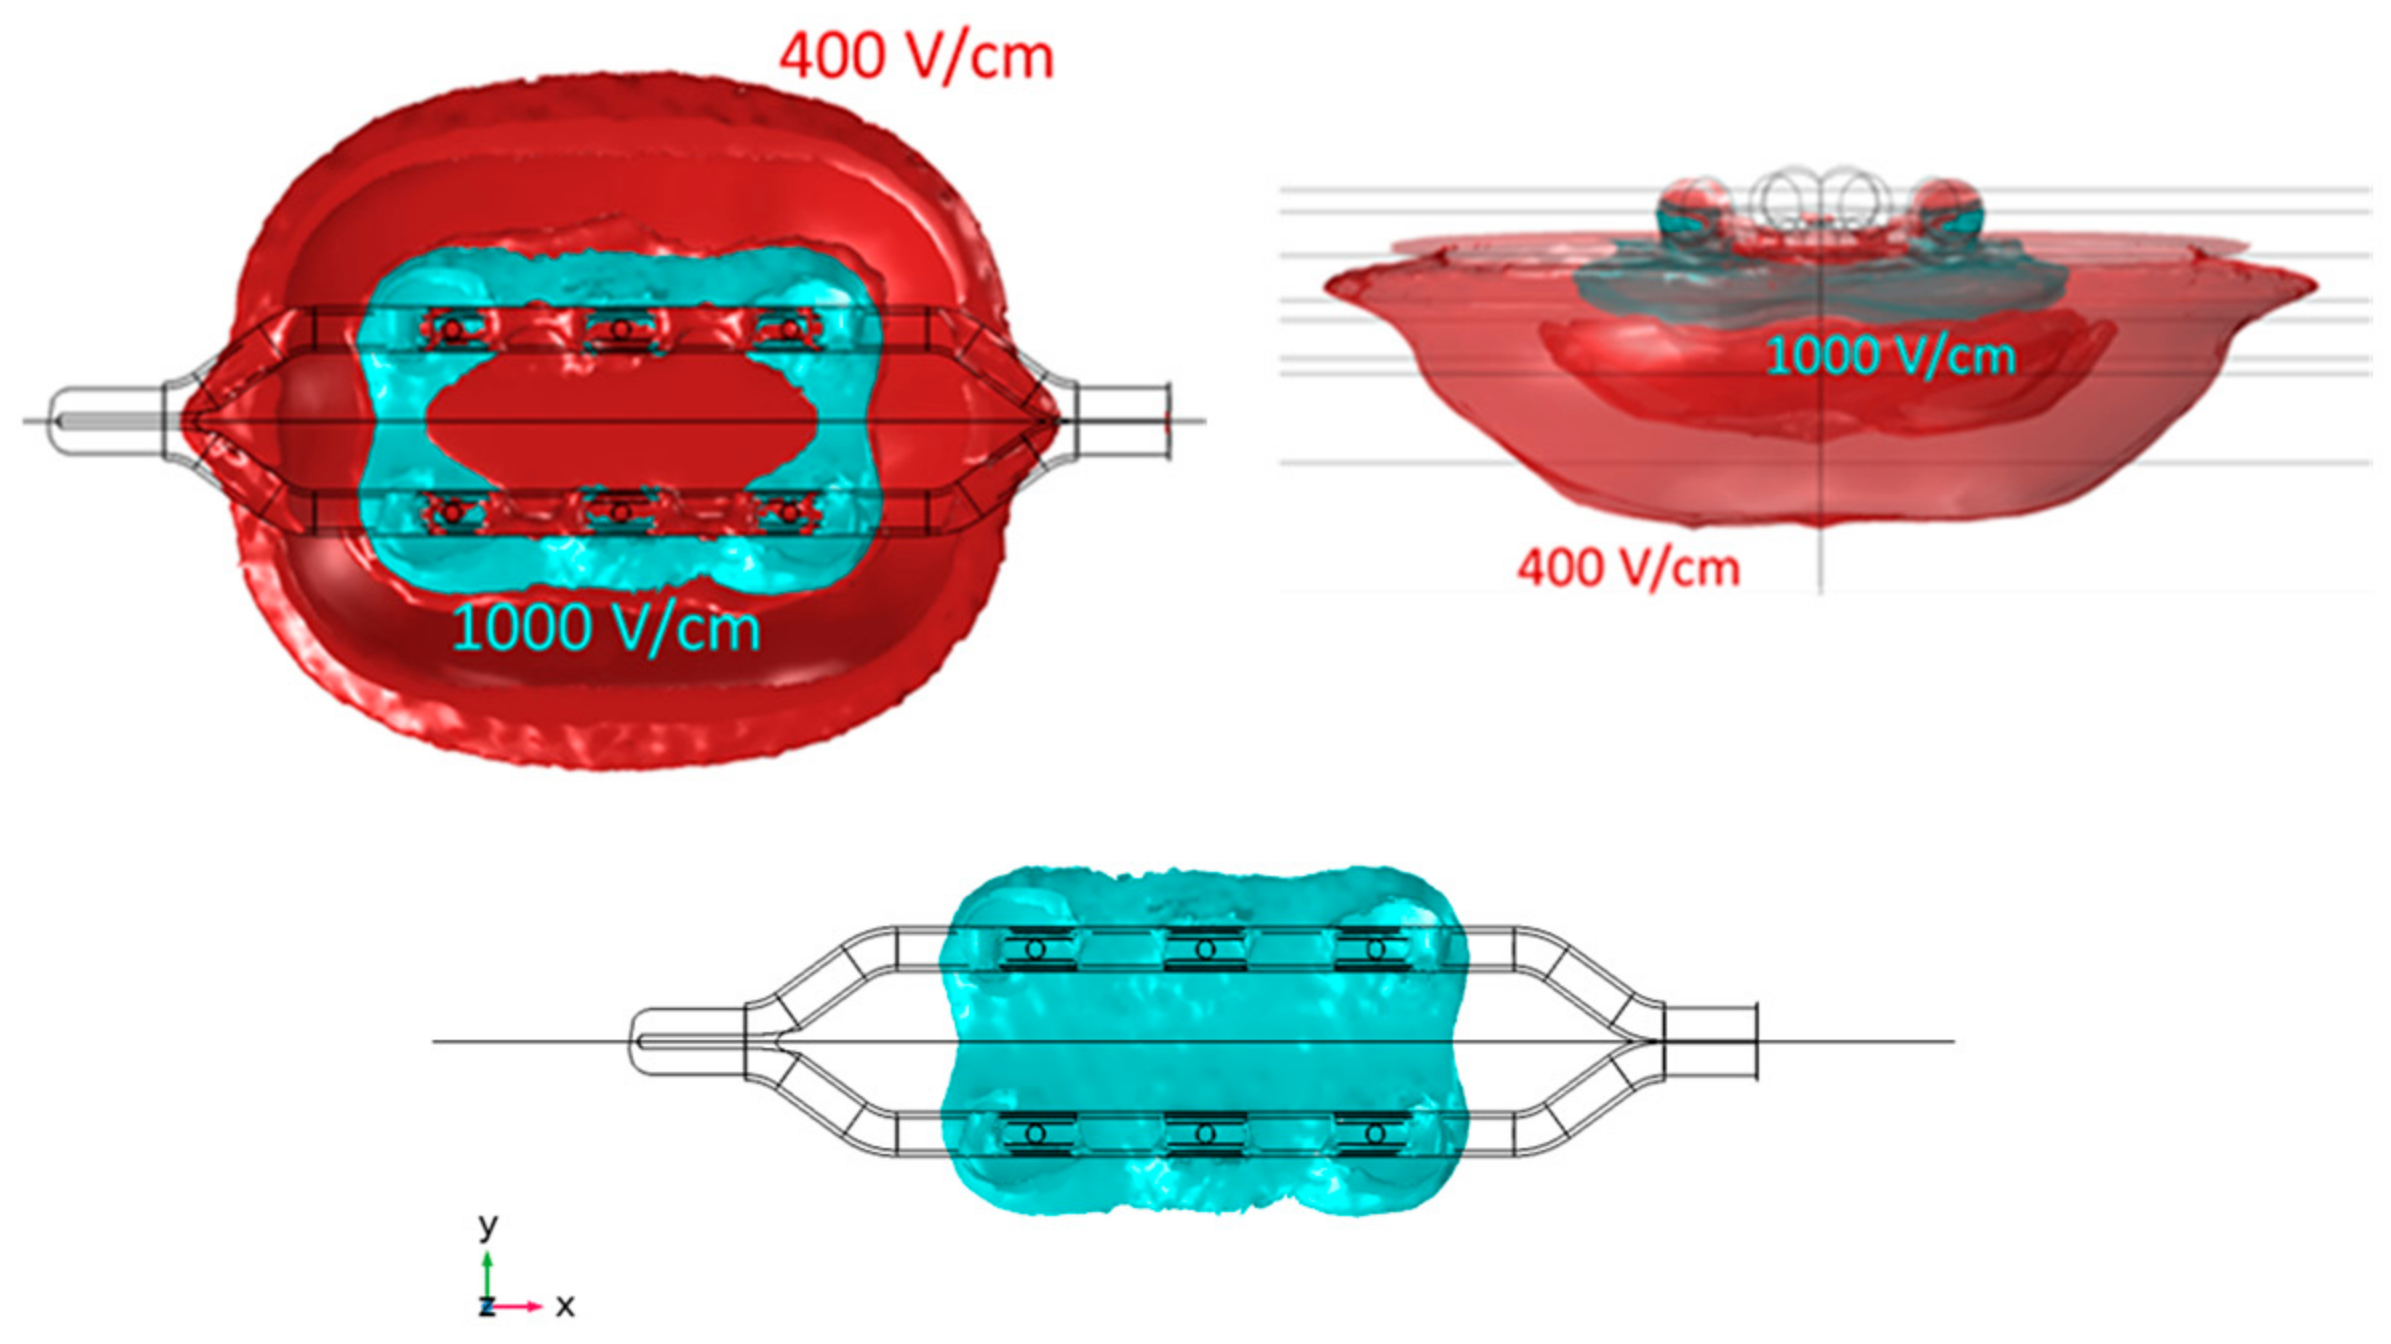

2.2. Electric Field Modeling

3.1. Electric Field Models